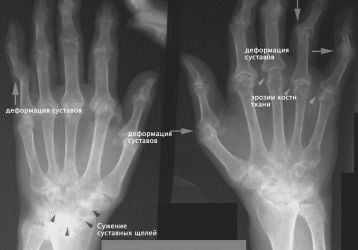

Симптомы и лечение основных болезней суставов рук: список распространенных

Распространенные болезни суставов рук: симптомы и лечение народными и традиционными способами. Перечень диагнозов для терапии.